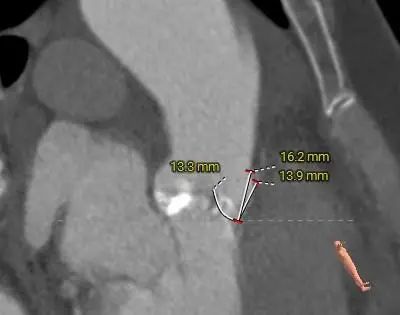

左冠脉开口高度偏低,左冠切线角度测量瓣叶小于LCA开口下缘到根部距离,右冠脉显影不佳,右冠切线角度测量瓣叶小于RCA开口下缘到根部距离。

LEFT CORONARY

RIGHT CORONARY

LCA&LEAFLET

RCA&LEAFLET